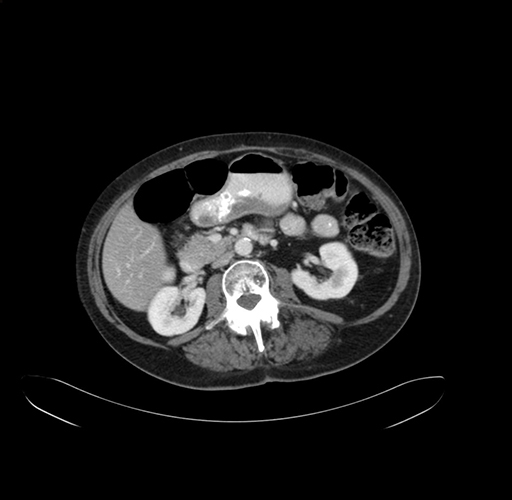

Axial Venous